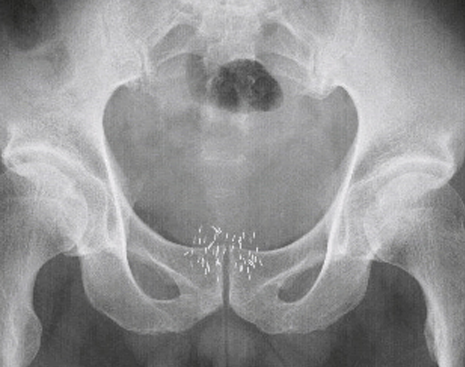

小線源(ヨウ素125)挿入後の骨盤部単純X線画像

低線量率永久挿入組織内照射法は、通常、数ミリの小線源50~80本程度を、会陰部から前立腺に埋め込んでいきます。3~4日程度の入院が必要になります。